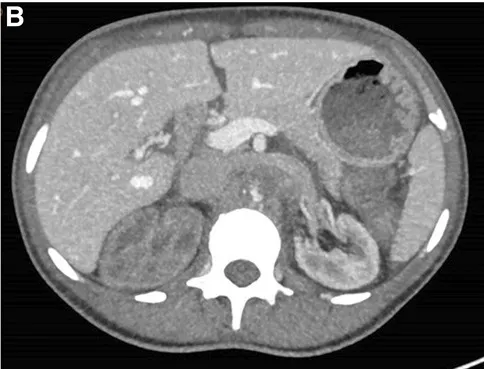

La TC también reveló una importante circulación colateral en la pared abdominal, lo que permitía un suministro sanguíneo suficiente a las extremidades inferiores. Solo el riñón izquierdo mostró captación residual de contraste (Figura 1), lo que sugería un riñón derecho isquémico.

TC con contraste (reconstrucción 3D) mostrando oclusión aguda de la aorta justo superior a la arteria mesentérica. (A) Oclusión aórtica justo superior a la arteria mesentérica (marcada con un ⊗) junto con vasos colaterales en la pared abdominal (B) Riñón izquierdo con realce de contraste y riñón derecho sin realce, lo que sugiere falta de perfusión renal.